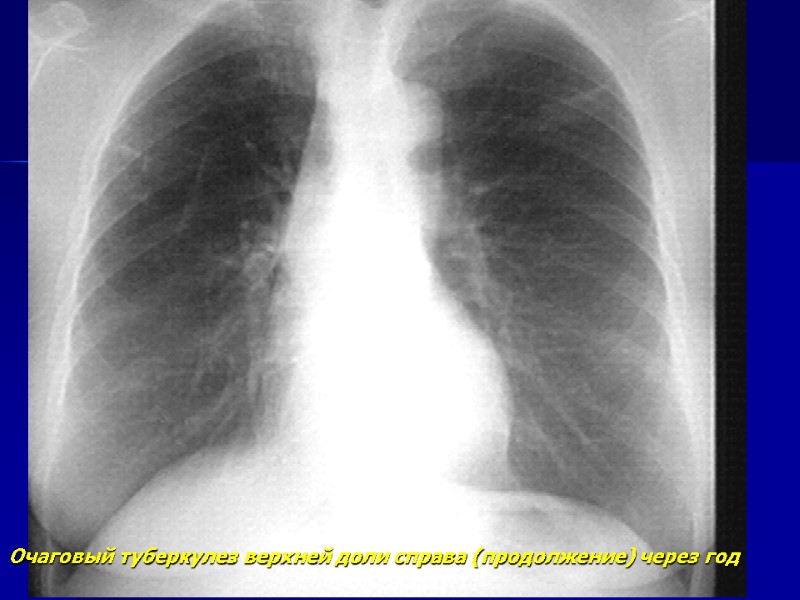

Очаговый туберкулез верхней доли справа

Очаговый туберкулез верхней доли справа (продолжение) через год